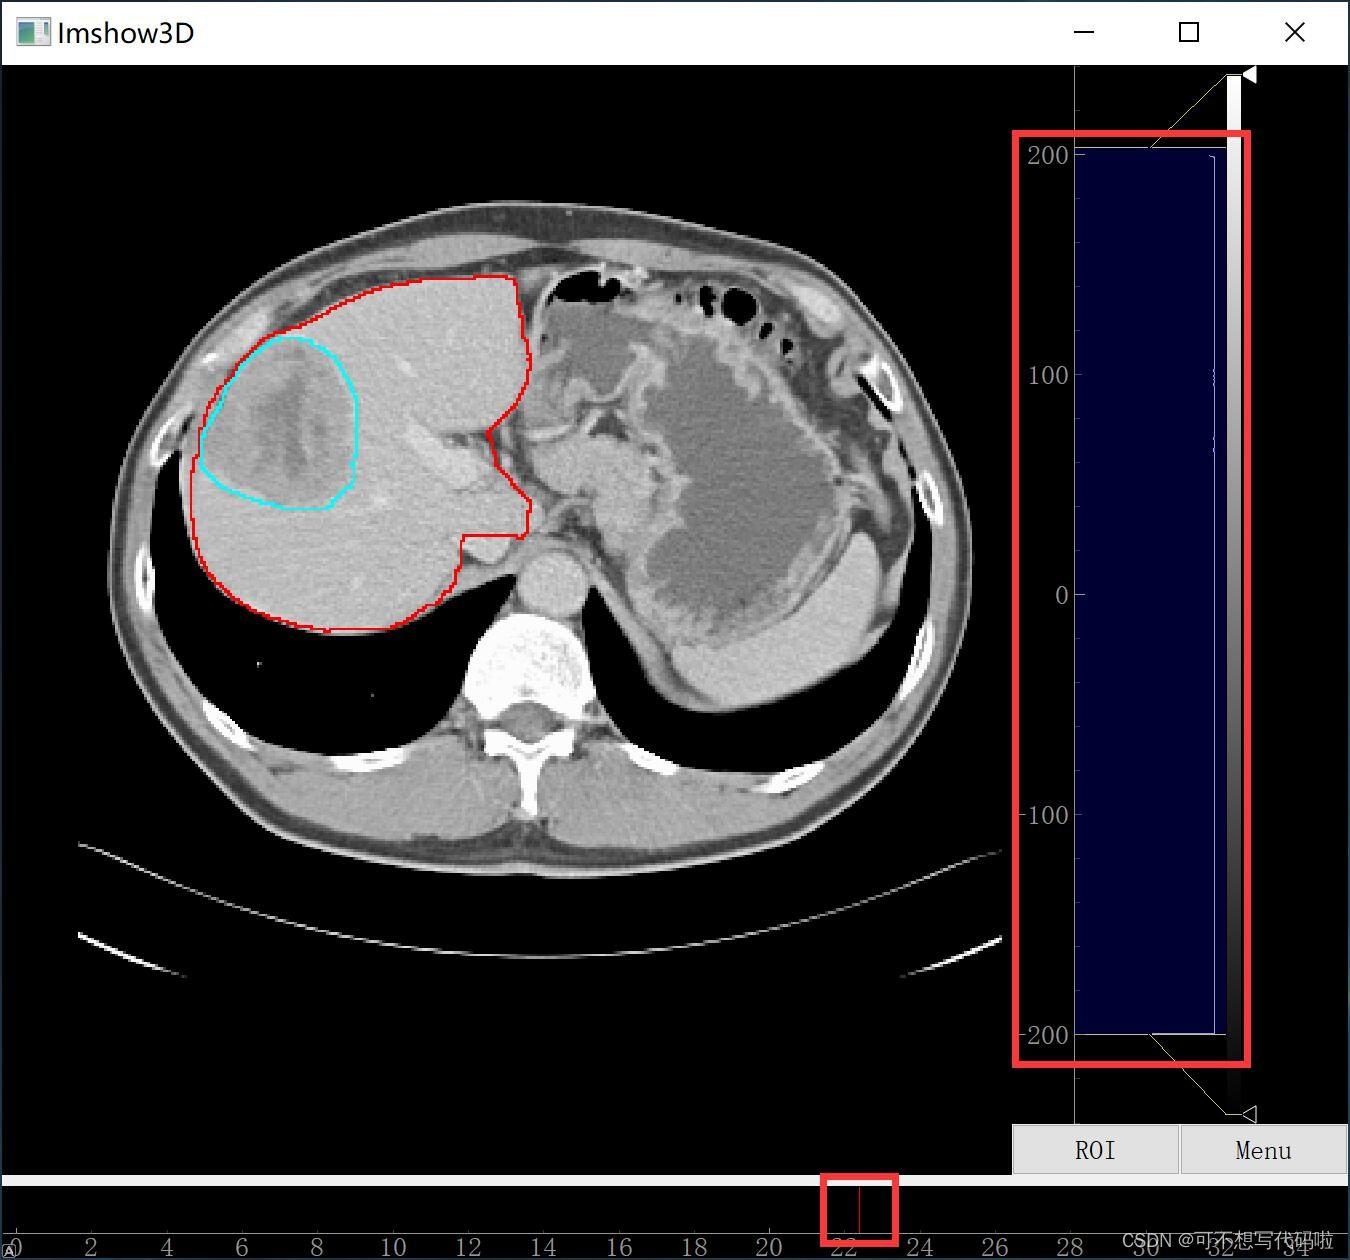

原文:我给出了两个代码,一个是可以同时显示器官、器官分割结果、肿瘤分割结果的,另一个是只显示器官的。当然,大家可以在第一个的基础上做改动。与 ITK-SNAP 不同,在显示的时候只显示分割结果的边界,这样更有利于观察分割的是否合理。并且还可以通过调节上图中右边红框中的滑块来调节图像灰度值的范围,通过调节上图中下方红框中滑块来查看不同横截面的图像。